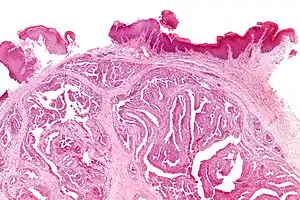

乳突状汗腺瘤

乳突状汗腺瘤(英語:),也成乳头状汗腺瘤(英語:),是一种界限清晰的乳腺组织异位肿瘤,经常发现于大阴唇。

它通常为原发性肿瘤(非癌症性),但是因为其倾向于溃烂,常被诊断为外阴癌。从组织结构学角度,它通常被定义为与乳腺管内乳头状瘤一类的疾病[1]。

中度顯示影像

極高度顯示影像